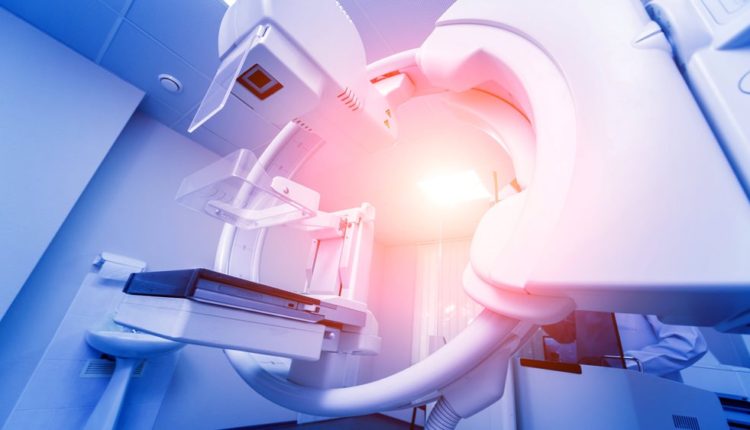

Ψηφιακή τομοσύνθεση μαστού: Ο ρόλος της στην έγκαιρη διάγνωση του καρκίνου του μαστού

Η διάγνωση του καρκίνου του μαστού σε αρχικά στάδια αποτελεί τον σημαντικότερο παράγοντα για τη βέλτιστη αντιμετώπιση και την πρόγνωση των ασθενών. Η ψηφιακή μαστογραφία 2 διαστάσεων αποτελεί την καθιερωμένη κλινική πρακτική προσυμπτωματικού ελέγχου για τη διάγνωση του καρκίνου του μαστού. Η ψηφιακή τομοσύνθεση μαστού δημιουργεί ψευδο-τρισδιάστατα σύνολα δεδομένων του μαστού από τα οποία μπορούν να ανακατασκευαστούν συνθετικές μαστογραφίες. Αυτή η καινοτόμος προσέγγιση μειώνει την πιθανότητα επικάλυψης των ιστών του μαστού που μπορεί να κρύψουν χαρακτηριστικά κακοήθειας.

Η πολυκεντρική μελέτη TOSHYMA που δημοσιεύτηκε πρόσφατα, έδειξε ότι η ψηφιακή τομοσύνθεση μαστού με ανασύνθεση μαστογραφίας 2 λήψεων είναι υπέρτερη όσον αφορά τη διάγνωση του καρκίνου του μαστού. Η μελέτη συμπεριέλαβε 99,689 γυναίκες ηλικίας 50-79 ετών που υπεβλήθησαν είτε σε κλασσική ψηφιακή μαστογραφία είτε σε ψηφιακή τομοσύνθεση μαστού.

Το ποσοστό ανίχνευσης καρκίνου ήταν 7.1 ανά 1,000 γυναίκες για την ψηφιακή τομοσύνθεση και 4.8 ανά 1,000 γυναίκες για την ψηφιακή μαστογραφία. Αξίζει να σημειωθεί ότι η ψηφιακή τομοσύνθεση μαστού ήταν υπέρτερη της ψηφιακής μαστογραφίας και όσον αφορά τη διάγνωση καρκίνου αρχικού σταδίου με ποσοστό ανίχνευσης 5.1 έναντι 3 καρκίνων ανά 1,000 γυναίκες.

Τα ευρήματα της παραπάνω μελέτης συνόψισαν για εμάς οι Καθηγητές της Ιατρικής Σχολής του Εθνικού και Καποδιστριακού Πανεπιστημίου Αθηνών, Φλώρα Ζαγουρή (Αναπληρώτρια Καθηγήτρια Παθολογικής Ογκολογίας, Νοσοκομείο Αλεξάνδρα), Ευαγγελία Πανουργιά (Λέκτορας Ακτινολογίας, Α’ Εργαστήριο Ακτινολογίας, Νοσοκομείο Αρεταίειο), Γεώργιος Ζωγράφος (Καθηγητής Χειρουργικής, Νοσοκομείο Ιπποκράτειο) και Θάνος Δημόπουλος (Καθηγητής Θεραπευτικής-Αιματολογίας-Ογκολογίας, Νοσοκομείο, Πρύτανης ΕΚΠΑ).